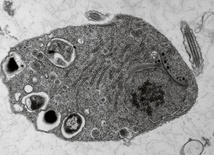

- Wiadomo, jak edytować DNA mitochondriów